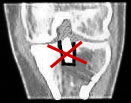

Immerhin scheinen meine Knochen eine Art Schnellheilungsmechanismus zu haben: Nur 5 Wochen nach der Korrekturoperation ist der Knochen schon fast wieder ganz verheilt - im folgenden Bild aus dem Inneren des Knies ist links das Bild vom 3. Mai, rechts jenes vom 7. Juni. Das versetzte Stück der Eminenz ist fast wieder fest drin; die Lücke beim Pfeil hat sich deutlich verkleinert - Krücken ade, Schmerzen leider noch nicht ganz. Das Streckdefizit beträgt immer noch 12 Grad.